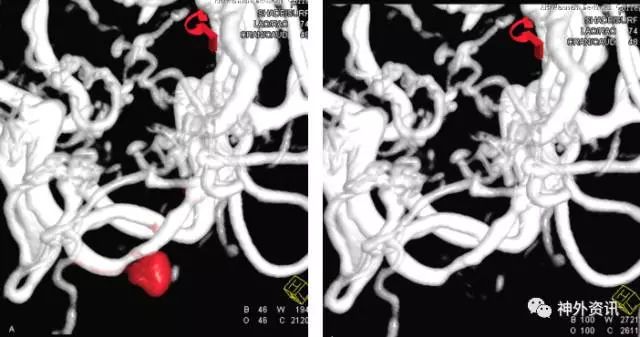

1例右侧额叶AVM伴右侧额叶血肿

(挑战:终末血管供血,超选距离遥远,途经血管迂曲,选择使用Envoy DA)

(Envoy DA导引导管—右侧大脑前动脉A1段)

(成功超选,栓塞后拔管顺利)

栓塞术后畸形团少量残留,静脉引流通畅,后2期行手术切除,术后复查脑血管造影畸形团未见明显残留。